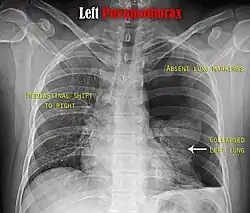

Chest X-ray

A plain chest radiograph, ideally with the X-ray beams being projected from the back (posteroanterior, or "PA"), and during maximal inspiration (holding one's breath), is the most appropriate first investigation.[35] It is not believed that routinely taking images during expiration would confer any benefit.[36] Still, they may be useful in the detection of a pneumothorax when clinical suspicion is high but yet an inspiratory radiograph appears normal.[37] Also, if the PA X-ray does not show a pneumothorax but there is a strong suspicion of one, lateral X-rays (with beams projecting from the side) may be performed, but this is not routine practice.[18][22]

Chest X-ray showing the features of pneumothorax on the left side of the person (right in image)

It is not unusual for the mediastinum (the structure between the lungs that contains the heart, great blood vessels, and large airways) to be shifted away from the affected lung due to the pressure differences. This is not equivalent to a tension pneumothorax, which is determined mainly by the constellation of symptoms, hypoxia, and shock.[16]

The size of the pneumothorax (i.e. the volume of air in the pleural space) can be determined with a reasonable degree of accuracy by measuring the distance between the chest wall and the lung. This is relevant to treatment, as smaller pneumothoraces may be managed differently. An air rim of 2 cm means that the pneumothorax occupies about 50% of the hemithorax.[18] British professional guidelines have traditionally stated that the measurement should be performed at the level of the hilum (where blood vessels and airways enter the lung) with 2 cm as the cutoff,[18] while American guidelines state that the measurement should be done at the apex (top) of the lung with 3 cm differentiating between a "small" and a "large" pneumothorax.[38] The latter method may overestimate the size of a pneumothorax if it is located mainly at the apex, which is a common occurrence.[18] The various methods correlate poorly but are the best easily available ways of estimating pneumothorax size.[18][22] CT scanning (see below) can provide a more accurate determination of the size of the pneumothorax, but its routine use in this setting is not recommended.[38]

Not all pneumothoraces are uniform; some only form a pocket of air in a particular place in the chest.[18] Small amounts of fluid may be noted on the chest X-ray (hydropneumothorax); this may be blood (hemopneumothorax).[16] In some cases, the only significant abnormality may be the "deep sulcus sign", in which the normally small space between the chest wall and the diaphragm appears enlarged due to the abnormal presence of fluid.[19]